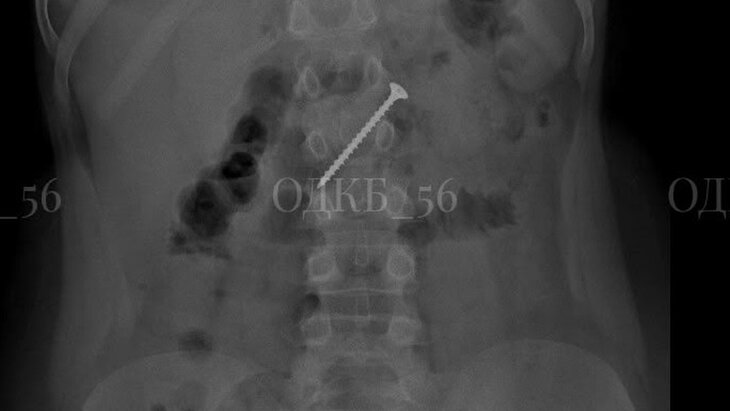

Фото: пресс-служба Областной детской клинической больницы города Оренбурга

Врачи Областной детской клинической больницы (ОДКБ) в Оренбурге оказали помощь 9-летнему ребенку, который во время игры случайно проглотил 5-сантиметровый саморез. Об этом сообщили в пресс-службе медучреждения.

По итогам обследования специалисты обнаружили крепежное изделие в двенадцатиперстной кишке мальчика. Застрявшее инородное тело представляло угрозу развития кишечной непроходимости и перфорации части пищеварительного тракта.